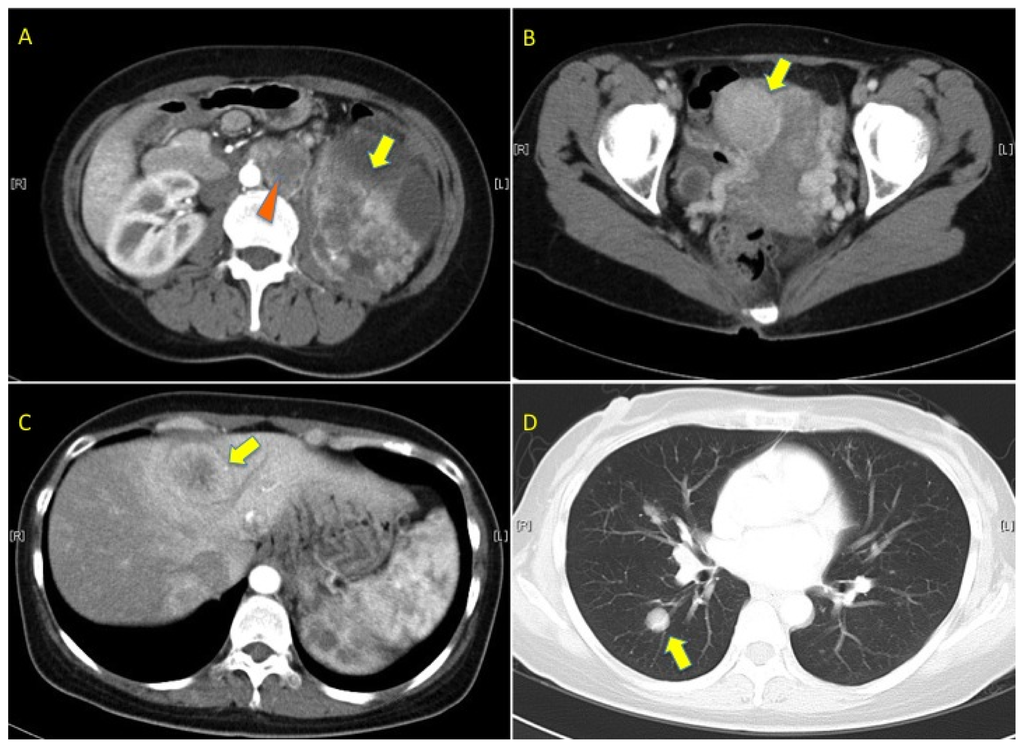

2. Case Presentation

2.1. Pedigree 1

2.2. Pedigree 2